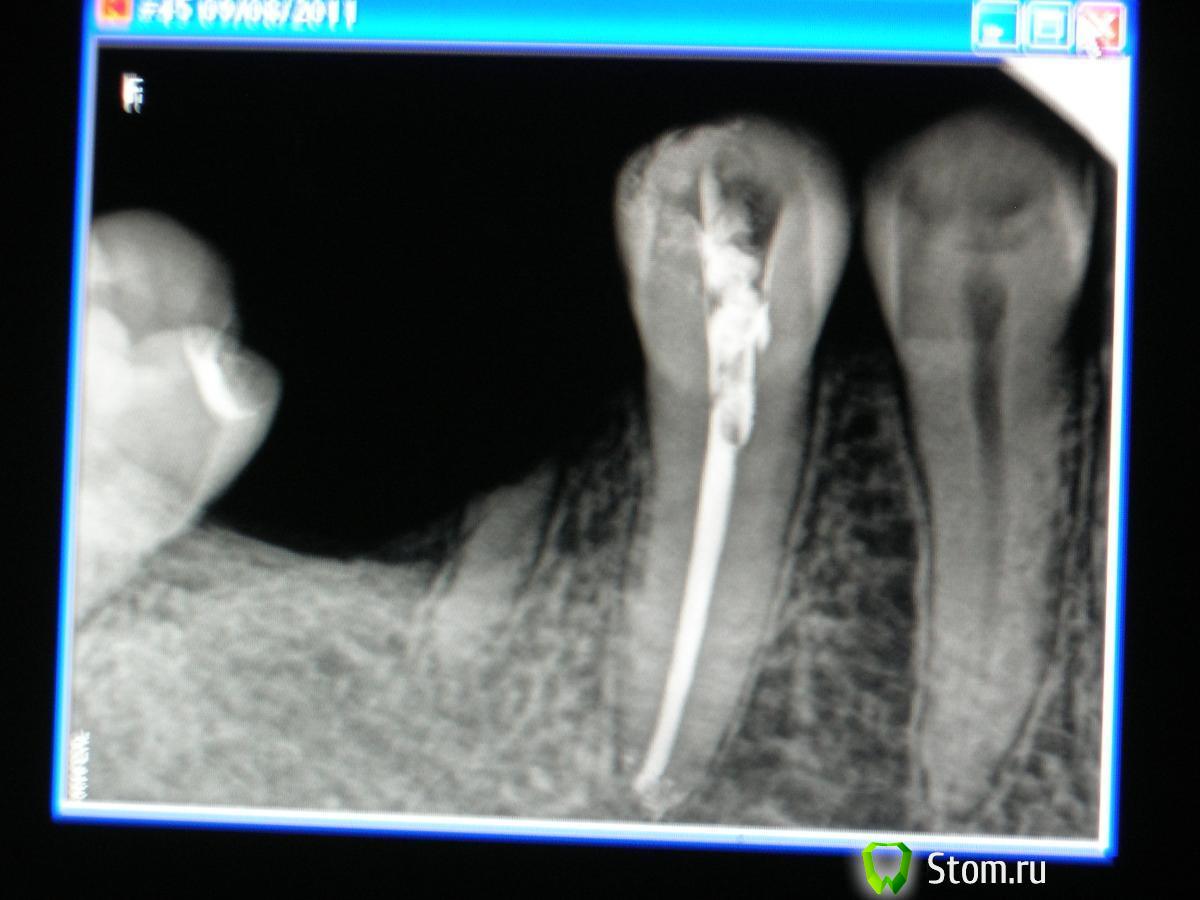

sabi Опубликовано 13 марта, 2012 Поделиться Опубликовано 13 марта, 2012 Дорогие,доктора !Помогите понять в чем причина болей.Начну с начала.В августе 2011 лечила 45 по поводу пульпита.вот контрольный снимок далее этот зуб стал одной из опор мостовидного протеза.Все хорошо,но в декабре появились боли сначала под протезом,а потом и в зубе.Появился свищ,в области межзубного сосочка между 45и46.Вот снимок-в свищ введен гуттаперчевый штифт В итоге мостик сняли,под ним ни пролежней,все чисто.Сейчас зуб беспокоит при накусывании,свищ не уходит,что это может быть?Ортопед настаивает,что я пропустила второй канал.Помогите советом.вот последний снимок Ссылка на комментарий

ger_berra Опубликовано 13 марта, 2012 Поделиться Опубликовано 13 марта, 2012 На пропущеный канал не похоже.На предмет наличия трещины надо проверить,согласна.Этот мост представляет собой рычаг,который постепенно вывихивает 45 зуб.Обратите внимание на периодонтальную щель дистально.Она расширена от коронки до апекса.Своеобразное ортодонтическое перемещение 45 в сторону 46 и одновременно функциональная перегрузка.Если уж и ставить в данном случае мост,то под опору нужно было взять и 44.Либо на место 46 имплант.Я так вижу. Ссылка на комментарий

ннэт Опубликовано 13 марта, 2012 Поделиться Опубликовано 13 марта, 2012 Причина может быть и не в трещине, и не в пропущенном канале, а банально в проталкивании распада за апекс во время инструментальной обработки. Посмотрите периодонтальную щель особенно со стороны 4го. Еще непонятный участок в обл удаленного корня, хотя на остаток не особенно похоже, но если свищ в этой обл. я бы точно сделала кюретаж. А гуттаперча точно в свище? у меня создалось впечатление что она под мостом Ссылка на комментарий

Каплан Опубликовано 13 марта, 2012 Поделиться Опубликовано 13 марта, 2012 (изменено) ну судя по наклону моляра, это все же 8, а не 7. слишком много места для одного моляра при таком наклоне дистальной опоры.+1 за трещину - условия есть (анкер). Прощупайте борозду по кругу шаг за шагом, каждый миллиметр... должен быть одиночный резкий карман. особенно медиально... слишком в этом месте расширение щели... Если трещины нет, возможно просто функциональная перегрузка... Изменено 13 марта, 2012 пользователем Каплан Ссылка на комментарий